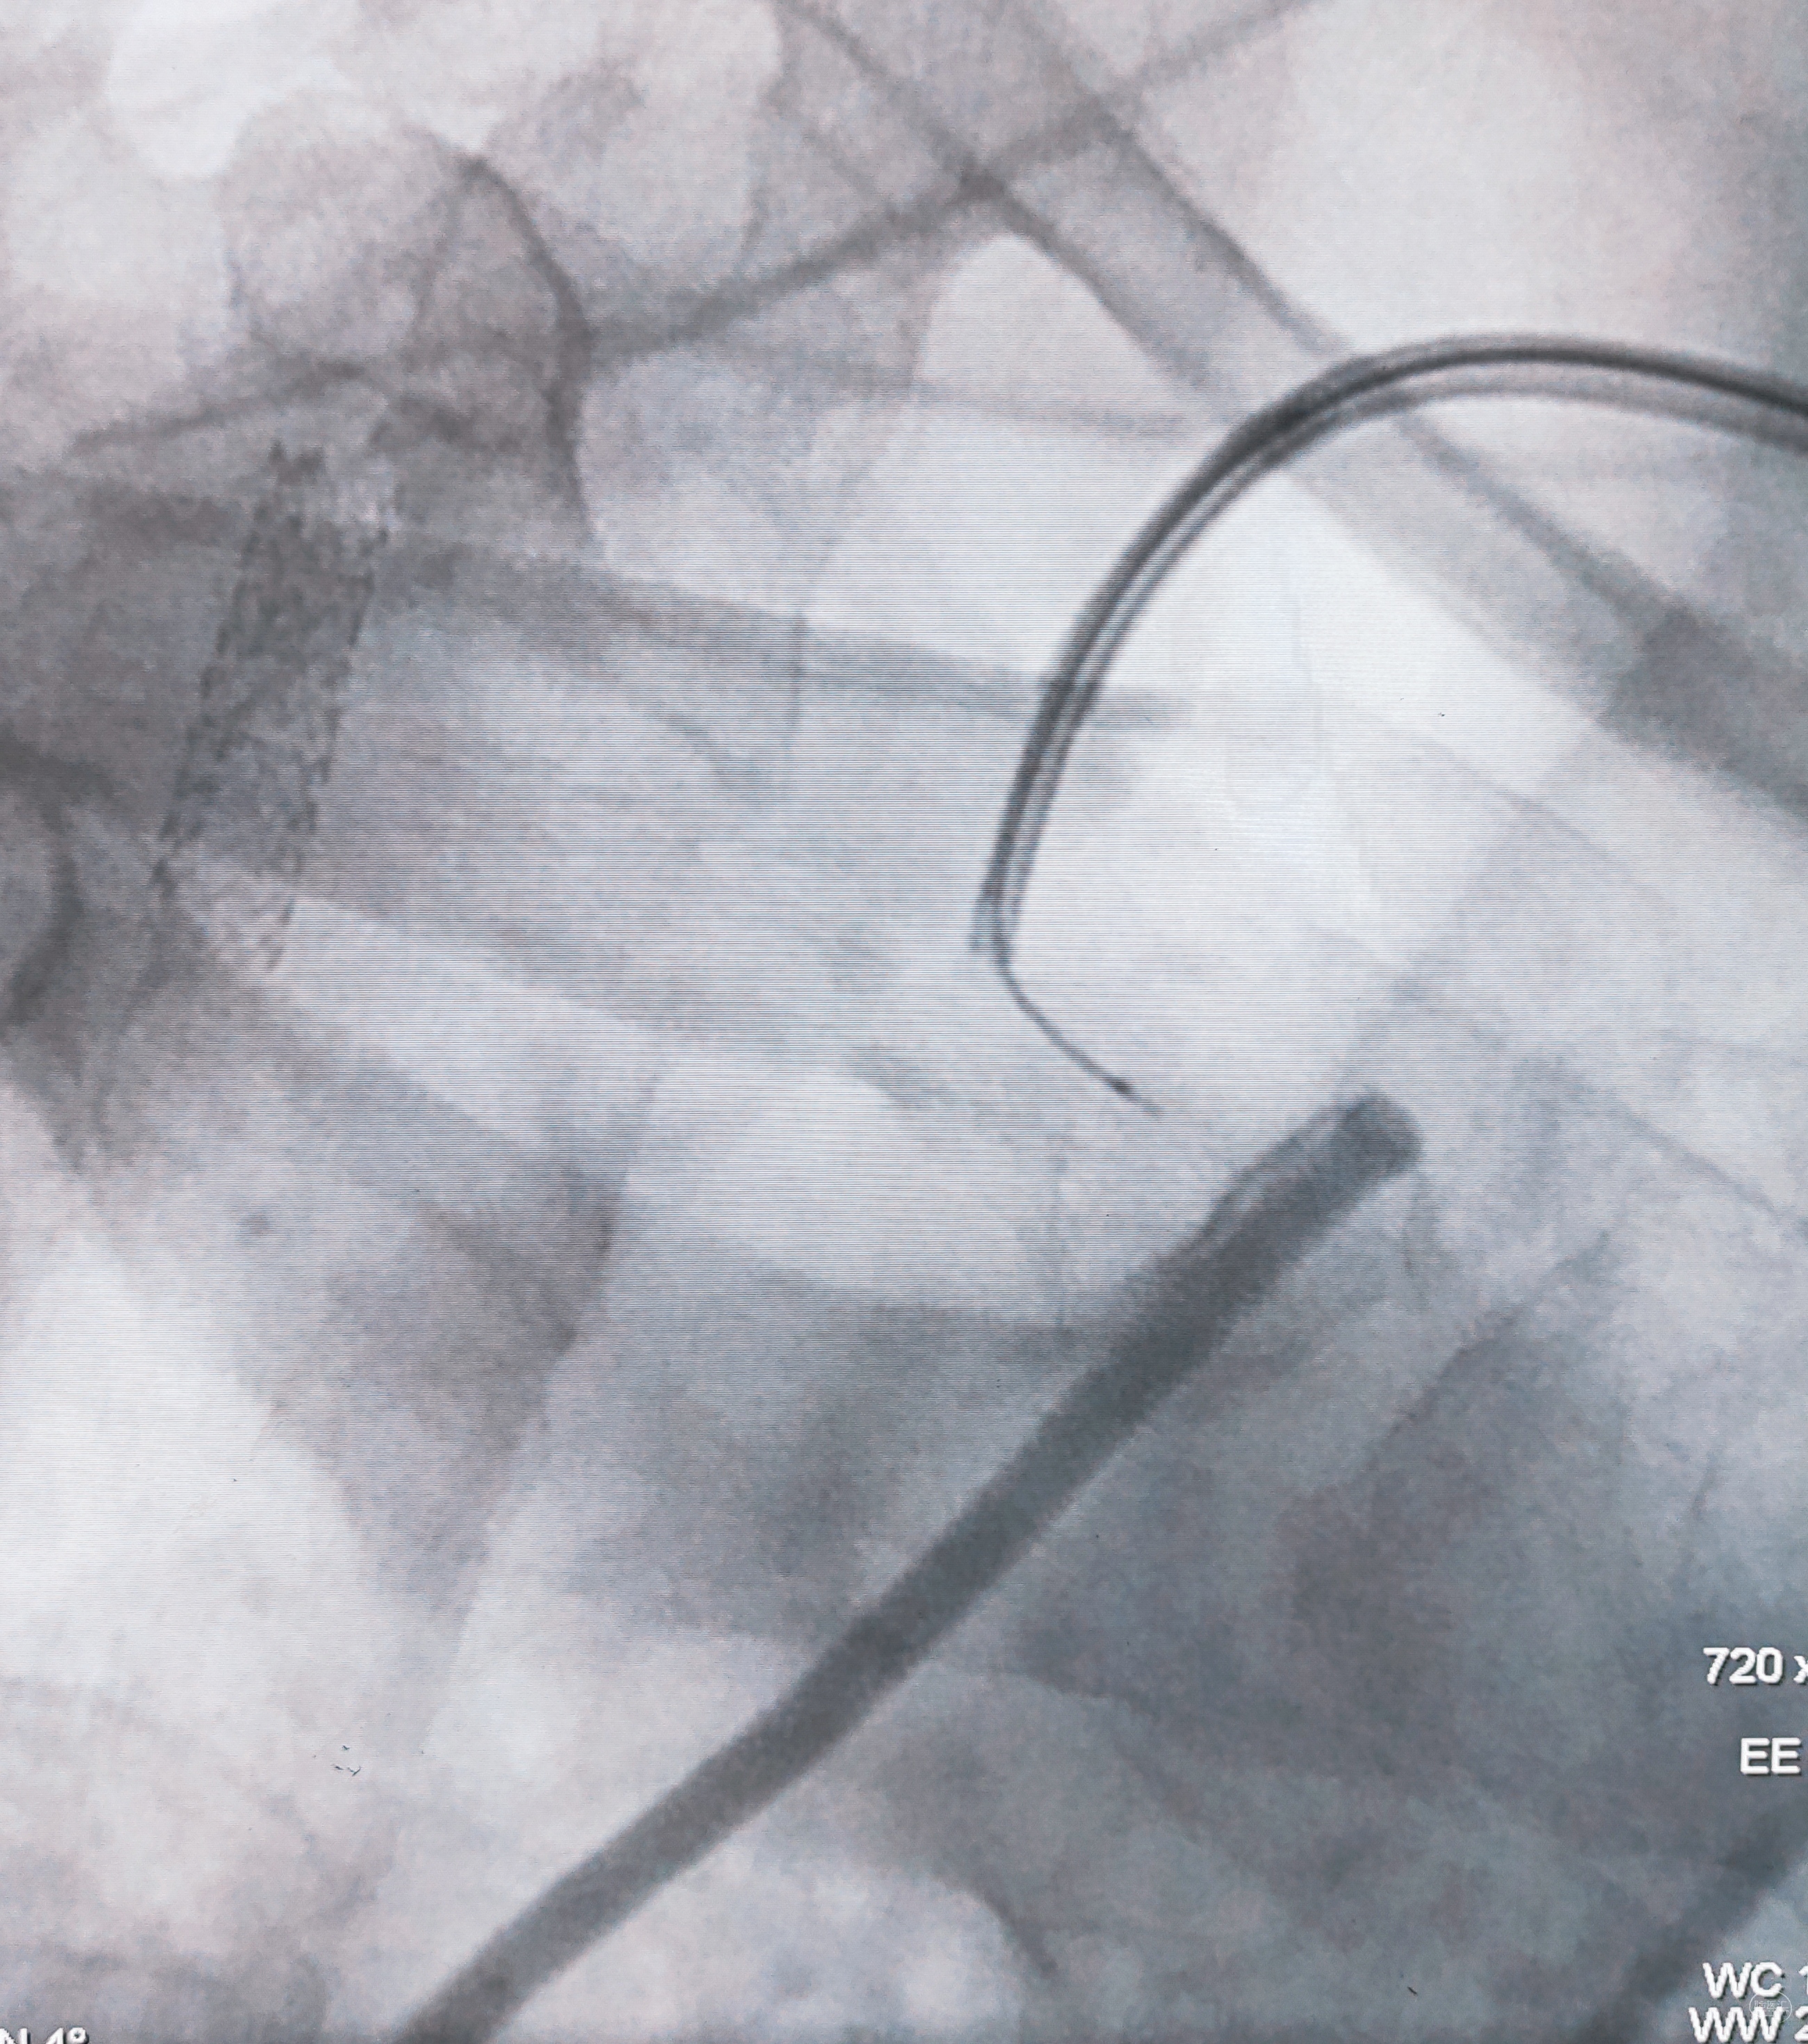

故事从接到一个来自上海区号的电话开始,询问得知,女儿在上海工作,特意返回山西晋中老家,带父亲一起来西安看病(感慨:孝顺女儿)。

如约初诊:女儿彬彬有礼,父亲中年男性,52y,间断头晕不适多年,口服药物效果不佳,遂在外院做了脑血管造影,推荐过来做脑血管搭桥。调取DSA影像后感觉血管比口述的情况复杂,远不是搭桥能够解决问题,毕竟是“头晕”为主诉,下面结合图像,分述如下:

弓上造影初见:问题(一)左侧锁骨下动脉闭塞,主诉为头晕,双上肢收缩压差>20mmHg,这就是祸根?接着看弓上造影晚期像。

弓上造影晚期:剂量因素,逆流盗血隐隐可见,复合预期,那就看看对侧椎动脉情况吧

右侧锁骨下造影:右侧椎动脉开口也是重度狭窄,血流速度缓慢,闸门效应明显,此刻,不禁感叹血管的伟大,自己都狭窄得不要不要的了,还努力给对侧代偿供血,奉献精神佳!

右侧颈总动脉正侧位造影:意料之外的是,枕动脉通过肌支与右侧椎动脉吻合(紫色箭头),像极了《大风吹》的歌词“借一杯天上的水”,源源不断进行着血流的补充。但是好景不长,同侧V4段明显狭窄,无情的设置了第二道坎(绿色箭头)。

左侧颈总动脉造影:颅内床突段以远基本闭塞,仅残涓涓细流,血供极差,脑膜中动脉瘤仅少量代偿,确实不容易,这估计就是想来搭桥的初衷了吧。

病情:

1,主诉“头晕”,双上肢收缩压差大

诊断:

1,右侧椎开口+V4段狭窄

2,左侧锁骨下闭塞

3,右侧颈内动脉床突段以远闭塞

分析:

1,主诉查体问题,应该还是后循环狭窄缺血引起

2,枕动脉虽有代偿,奈何其远端还有狭窄

治疗策略分三步走:

1,先解决右侧两处串联的狭窄,改善后循环血供,估计能显著改善主诉

2,择期开通闭塞的左侧锁骨下动脉,纠正盗血,改善上肢血流

3,左侧前循环问题根据前期治疗结果再议

规划完毕,说干就干